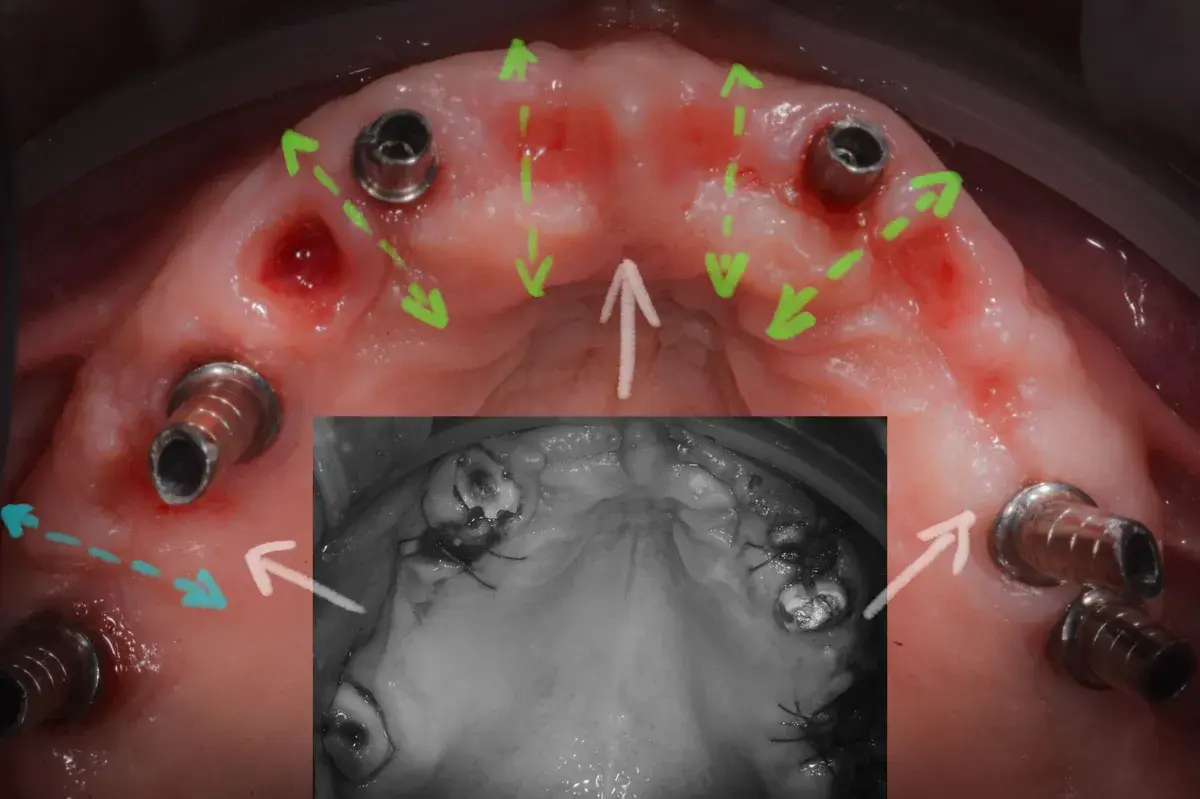

Cresta atrofica in zona 4.6 con difetto osteo-mucoso e cheratinizzata quasi assente: Bonebending 4.0 e impianto in unica seduta. Risultato a 3 mesi.

Tecniche di sutura e gestione della gengiva cheratinizzata attorno agli impianti. Perché la qualità dei tessuti molli è cruciale per la longevità implan...

Paper 2024 su Gingival Open-Wound Technique: "innovazione" o riscoperta? Dr. Bruschi documenta guarigione per seconda intenzione nell'implantologia da...

Scopri come il tuo corpo guarisce naturalmente senza suture. La guarigione per seconda intenzione: il processo che rigenera osso e tessuti per impianti ...